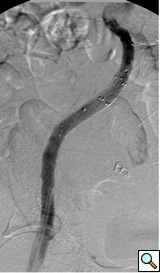

- In aneurysmal pathologies, it is important to cover the entire length of the aneurysm. The stent grafts are subsequently ballooned as suggested by the IFU. An IVUS interrogation of the entire stent graft is a helpful adjunct. This will detect any circumferential stent mal-apposition to the proximal or distal landing zone that may lead to endoleak. A completion angiogram is performed to confirm lack of gross endoleak. However a single arteriogram may miss endoleak due to projection overlap. A bi-plane arteriogram is more reliable in excluding any significant procedural endoleak.

- After the completion angiogram, the introducer sheath is removed while carefully leaving the wire in the vessel. If the patient remains hemodynamically stable, an intact iliac/femoral artery may be assumed. In majority of cases and with percutaneous technique, manual compression or vascular closure devices are used. In case of open femoral artery exposure, the wire is removed, and the femoral artery is repaired in standard fashion.